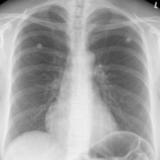

Biventricular ICD

Date: 10/22/2010

Views: 4396